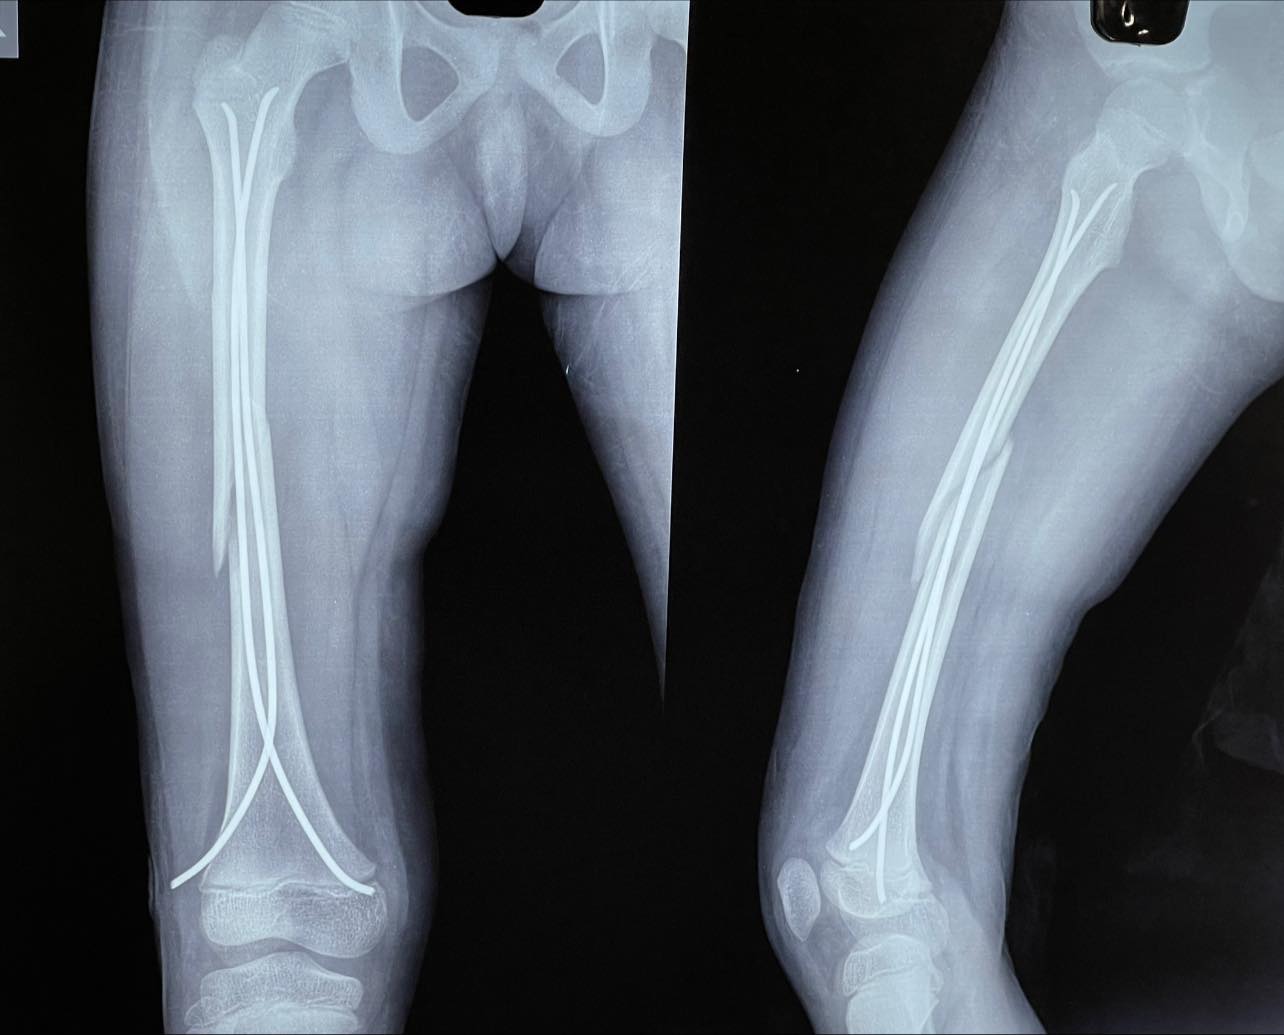

case in point: 6 yr old male with shaft of femur fracture treated with minimally invasive titanium elastic nails, in such cases, absolute picture perfect reduction is neither necessary nor often is possible, however, it would be hard for a surgeon to explain all this to the esteemed parar dada.

For all intents and purposes this will have a normal union and should leave no deformity or lasting future issues.